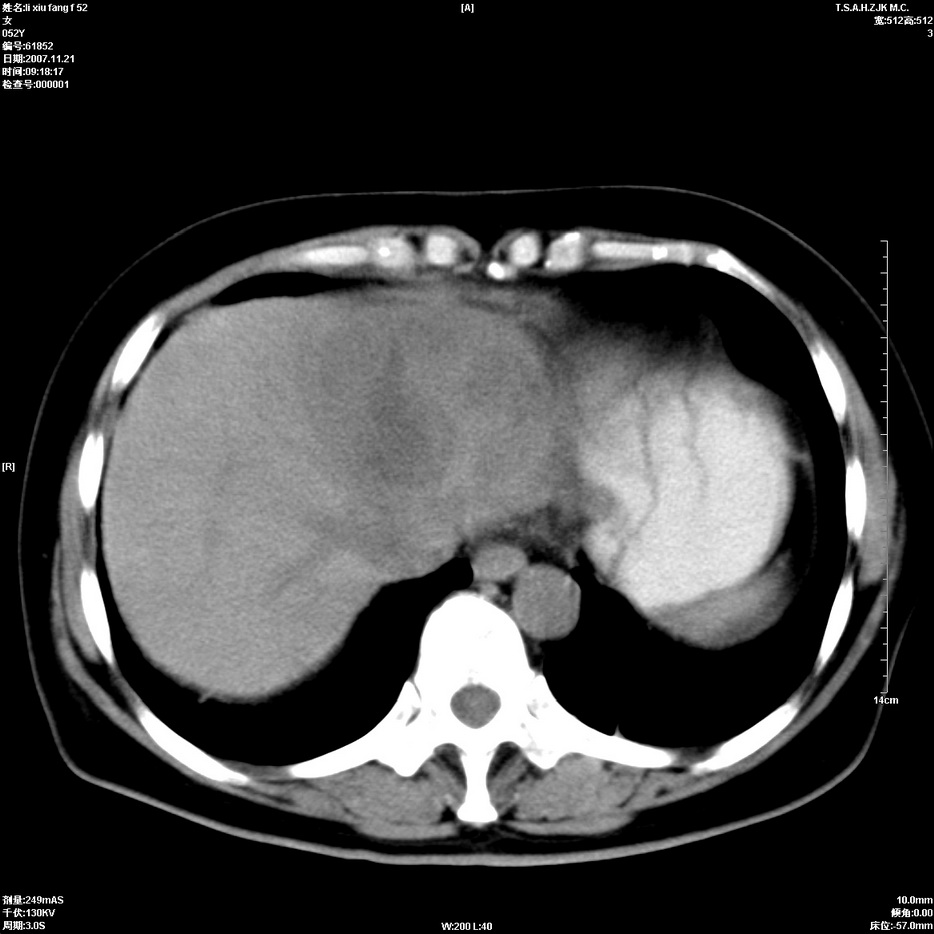

标题: CT12858:女,52岁,胎甲球蛋白861肝左叶占位,肝癌。下腔静 [打印本页]

标题: CT12858:女,52岁,胎甲球蛋白861肝左叶占位,肝癌。下腔静

肝左叶巨大低密度灶肿块,增强符合快进快出表现,有动静脉交通支;静脉期,下腔静脉内有充盈缺损,afp明显升高,支持肝癌并下腔静脉癌栓形成。

以下是引用拾荒者在2008-4-15 22:57:00的发言:[br]肝左叶巨大低密度灶肿块,增强符合快进快出表现,有动静脉交通支;静脉期,下腔静脉内有充盈缺损,afp明显升高,支持肝癌并下腔静脉癌栓形成。